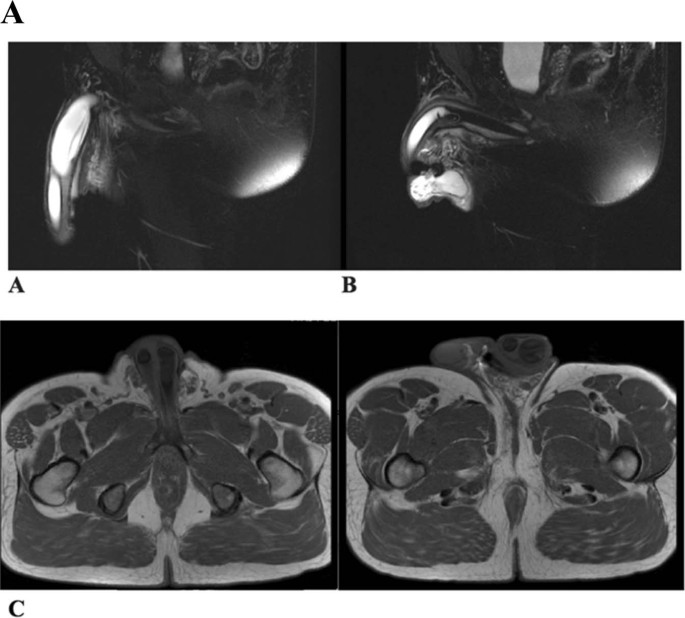

Auxiliary clinical workup was done in one patient who had delayed intervention whereby his condition worsened with device inoperability. His pelvic magnetic resonance imaging (MRI) study revealed proximal corporal dilatation and prosthetic cylinder aneurysmal dilatation, which was confirmed intraoperatively (Fig. 3).

Proximal corporal deformity is a unique IPP surgical complication. It may be challenging to recognize this complication, particularly in patients who present with IPP devices that seem operable. Vigilant clinical assessments followed by axial pelvic body imaging, such as MRI, may facilitate the detection of these penile soft tissues deformities and associated IPP defects in highly suspicious circumstances. We utilized MRI as an adjunctive diagnostic tool in one patient that also aided in surgical planning. Thiel et al. evaluated the use of T2-weighted MRI for different anatomical penile and IPP defects [12]. In this case series, they reported the use of MRI to detect a patient with aneurysmal dilatation and buckling of a prosthesis cylinder due to a preexisting corporal deformity. Preoperative familiarity with the penile wobble effect phenomenon may also assist in recognizing these deformities readily.